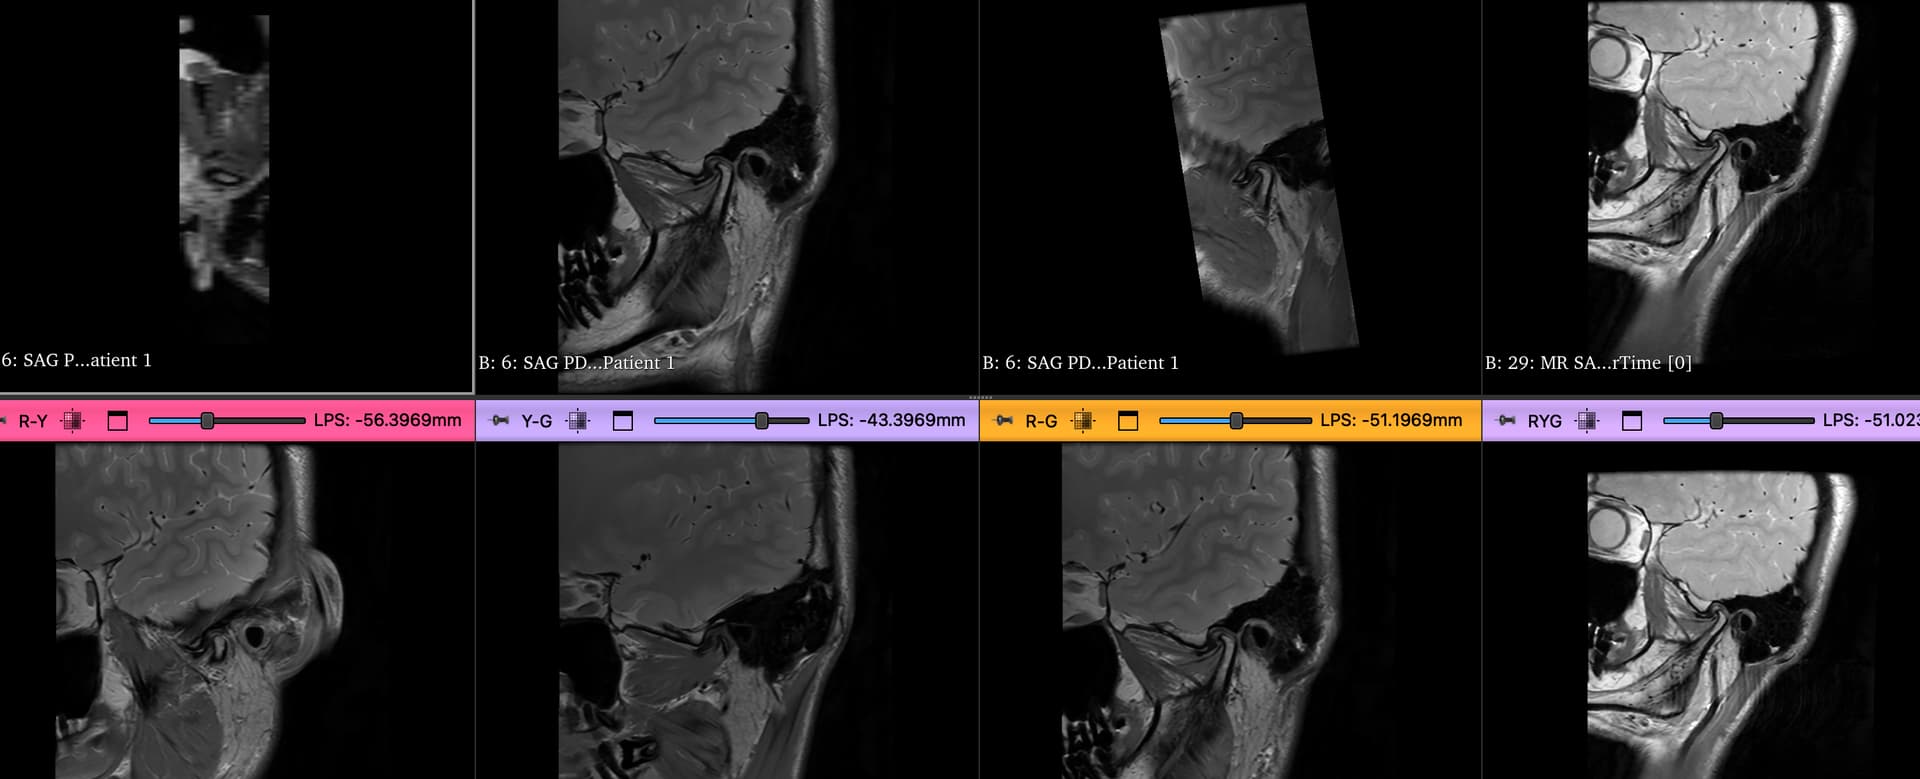

Tmj viewer module

im working on modeule for view tmj images especially mri . code vibing , zero coding skills or knowledge

now im at point of doing dual sagittal view and im trying to have independet slice intersection .

the idea to have full control over each series independently . i did many iteration with AI to work the code for it but its not going very well . im just wonder if this is actually possible in slicer.

im try to view each series into different orientation side by side . im also trying to have each view to be independent , i can move them without affecting others.

for example i do rotation and transform view without the second series being affected . bare in mind these are series from same volume.

in compare view i cant have indpendent control for each view . they seem to be synced which is not what i need